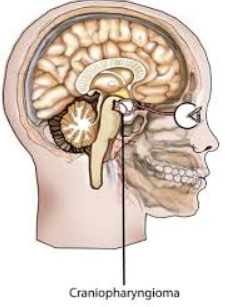

Post-chiasmal disorders are disorders associated with lesions of the optic chiasm, manifesting as various impairments of the sufferer's visual field according to the location of the lesion along the optic nerve. This condition can also be called chiasmal syndrome.

Post-chiasmal disorders may be associated with cognitive changes caused by the structural or functional alteration of the brain tissue, which are often associated with TBI. The alteration can lead to brain dysfunction which can manifest as a variety of visual impairments. Post-chiasmal disorders can also be a result of multiple sclerosis, stroke, TIA, or tumors.

Common causes of chiasmal syndrome can be placed into five categories - congenital, traumatic, iatrogenic, extrinsic lesions, or intrinsic lesions.